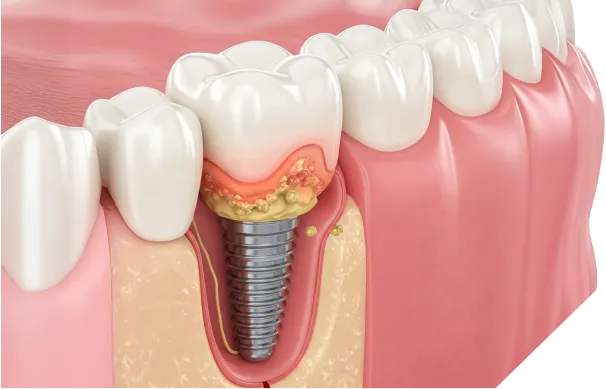

インプラント周囲炎

インプラントのリスクで最も注意すべきものが、歯周病菌への感染によって起こる「インプラント周囲炎」です。自覚症状がないまま進行し、最終的にインプラントを支える骨を溶かしてしまうことが、インプラントの寿命を縮める最大の原因です。

インプラント周囲炎の進行

- 1 初期

インプラント周りの歯茎が腫れる、出血する。この段階なら適切なケアで改善可能。

- 2 中期

炎症が顎の骨にまで広がり、骨が溶け始める。膿が出たり、インプラントがぐらついたりする。

- 3 末期

骨が吸収されてしまい、支えを失ったインプラントが抜け落ちてしまう。再治療が必要な状態。

当院の回避策

インプラント治療の成否は、メンテナンスにかかっていると言っても過言ではありません。当院では、治療後の定期的なプロフェッショナルメンテナンスを必須としています。セルフケアでは除去できない汚れを取り除き、周囲炎の兆候を早期に発見・対処することで、大切なインプラントを長く守ります。